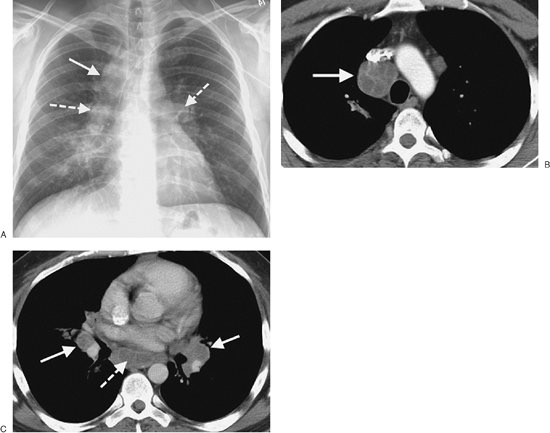

FIGURE 6-23. Pulmonary histoplasmosis. A: PA chest radiograph shows right paratracheal (solid arrow) and bilateral hilar (dashed arrows) lymphadenopathy. B: CT scan shows bulky right paratracheal lymphadenopathy (arrow). C: CT scan at a more inferior level shows bilateral hilar (solid arrows) and subcarinal (dashed arrow) lymphadenopathy. The appearance is indistinguishable from that of sarcoidosis.